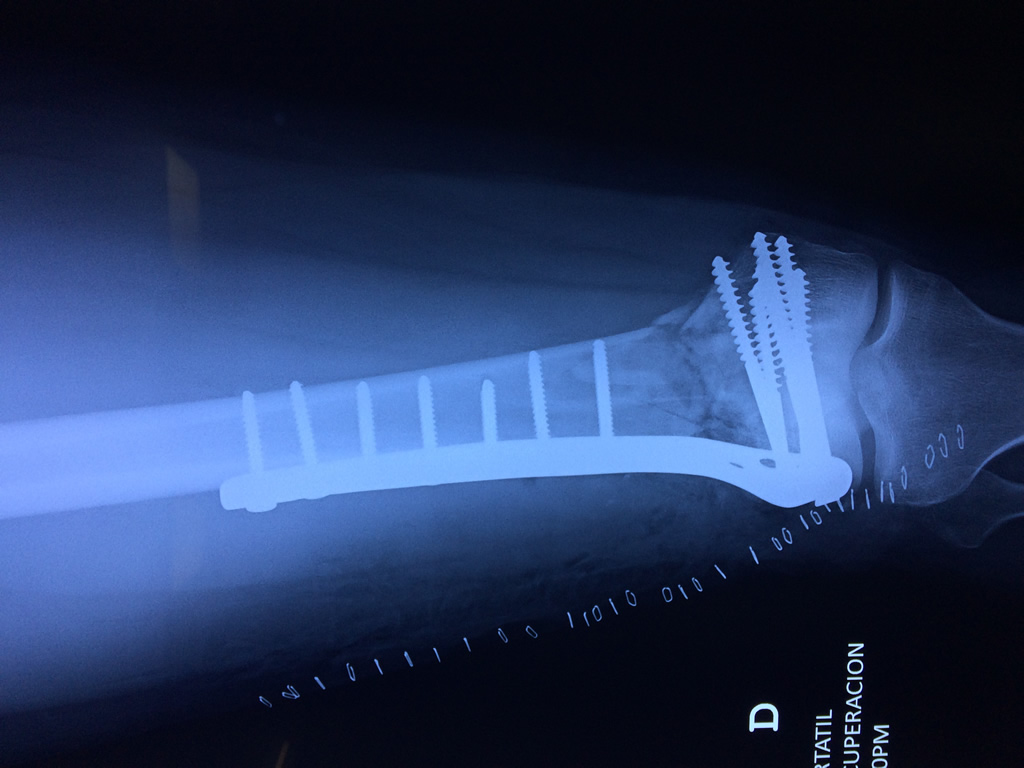

Cirugías de Calcaneo - Fémur

El fémur es el hueso del muslo, el segundo segmento del miembro inferior. Es el hueso más largo, fuerte y voluminoso del cuerpo humano.